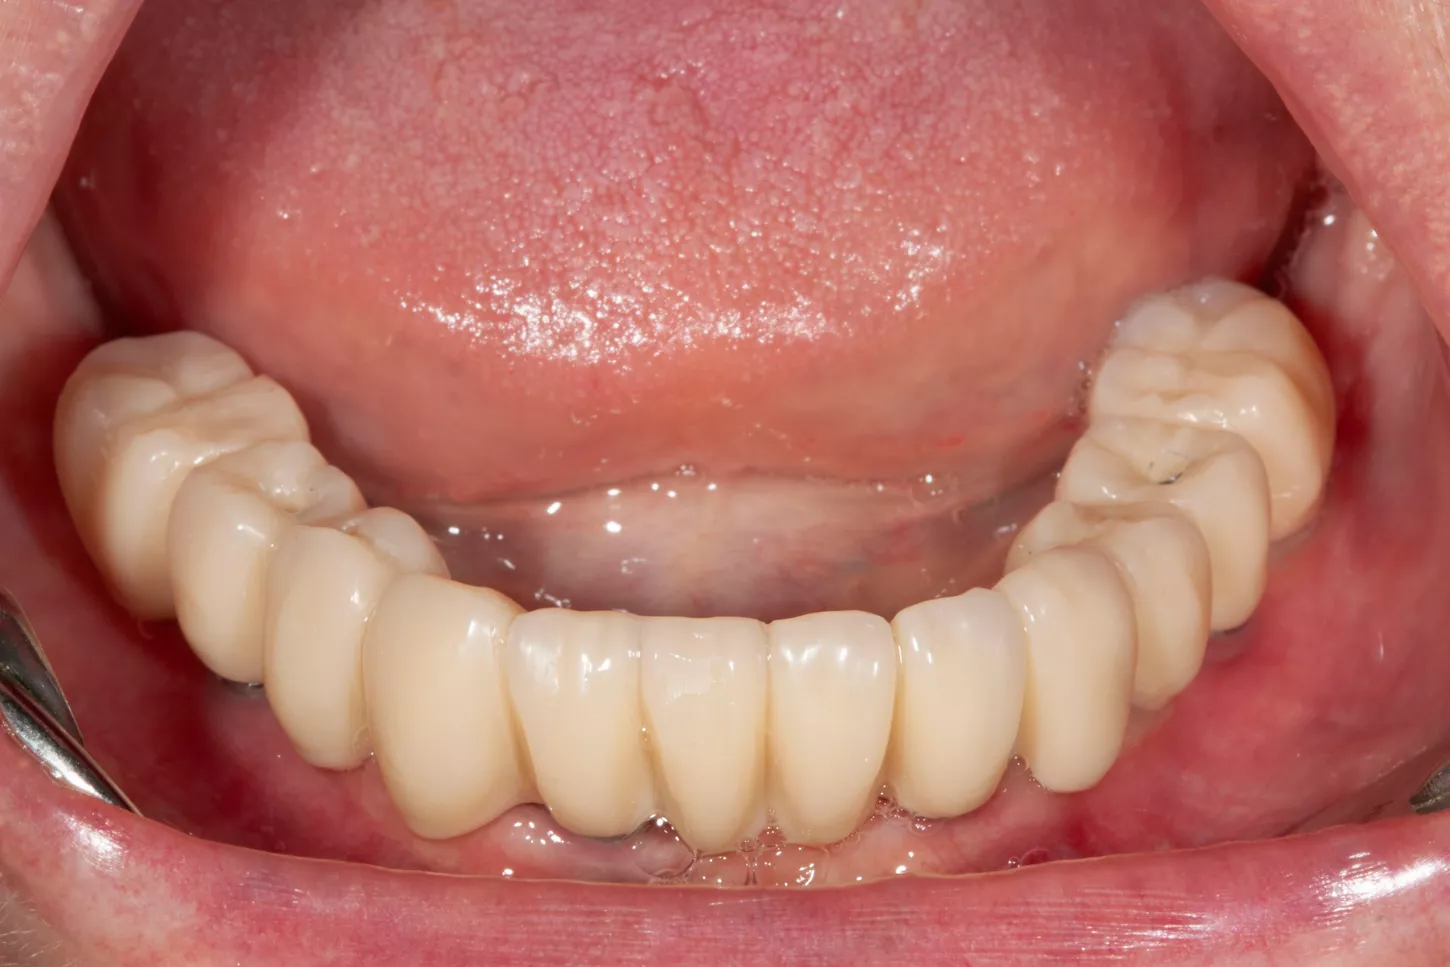

16. Display of the finished lower jaw work after osseointegration.